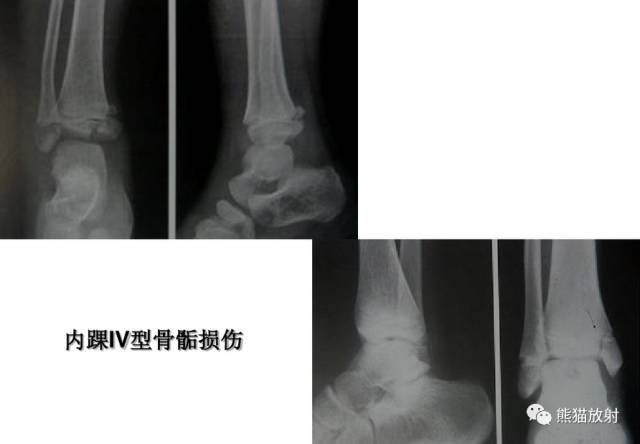

Salter-Harris IV型:骨折累及骺板、干骺端及骨骺,属于关节内骨折。

第四型(Ⅳ型) 骨骺和干骺端骨折。该型也较多见,仅次于第二型,占30.2%;骨折线呈斜形贯穿骨骺、骺板及干骺端,由于骨折线同过生长板全层,所以容易引起生长发育障碍和关节畸形,多见者为鱼尾状畸形。此型多见于10岁以下小儿的肱骨外髁及年龄较大儿童的胫骨远端,此型必须切开复位及内固定。